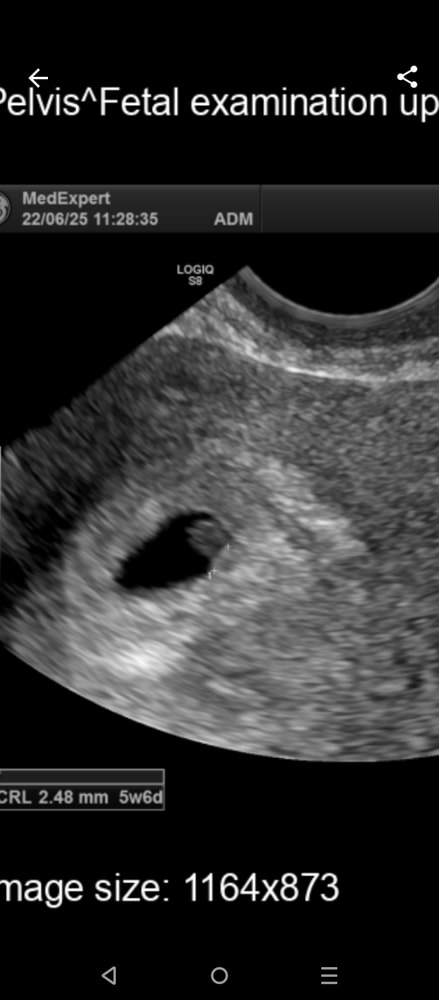

Марина, я прикрепила фото узи в комментариях

20-го хгч 6848, 22 по узи ктр 2,5. И она его заметила чудом вообще Изображениея бы не заметила

Изображение

Не понимаю как она опередила что беременность не будет развиваться